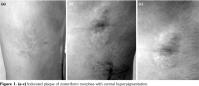

An 18-year-old healthy, male patient presented with complaints of hardness and discoloration of the skin at the right posteroinferior side of his trunk with a zosteriform distribution of T10-12 dermatomes, over a period of two years. We detected no characteristic finding in his medical/family history and physical examination except indurated plaque that measured 9x6 cm in diameter with central hyperpigmentation among the xyphoid and umbilicus that extended to the lateral part of the trunk with atrophic lesions in a zosteriform distribution (Figure 1). We detected no history of herpes zoster or other skin lesions on the site of ZM, abnormal skin moisture, suggestive signs of other extracutaneous, musculoskeletal or systemic sclerosis. Serology for varicella-zoster